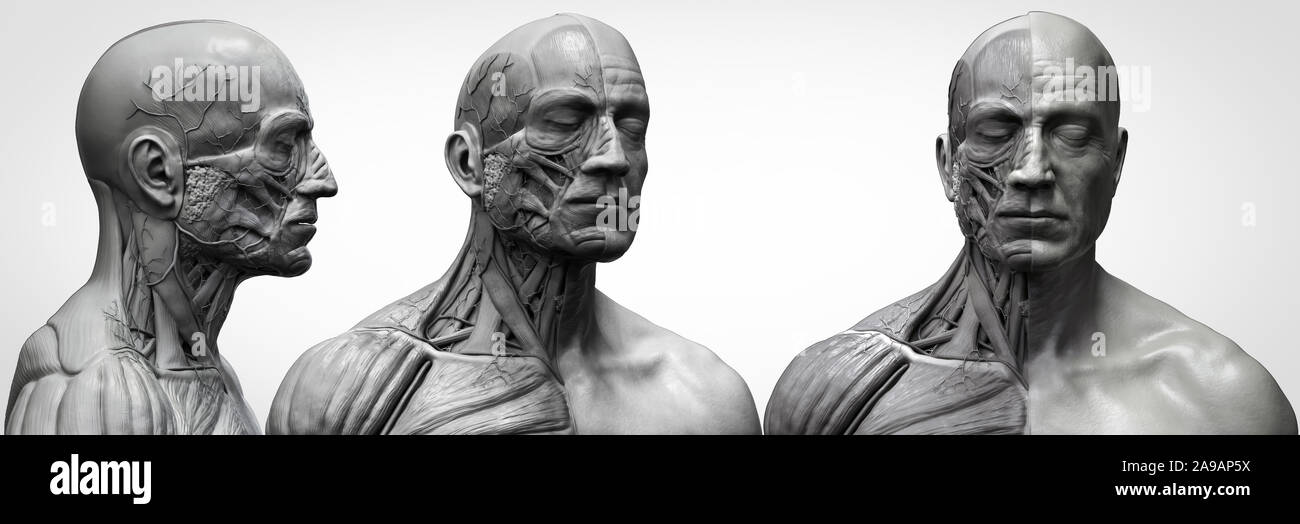

RF2A9AXYJ–Menschliche Körper Anatomie Muskeln Aufbau eines männlichen, Vorderansicht Seitenansicht und Perspektive, 3D-Rendering im Hintergrund

RF2A9AP5X–Menschliche Körper Anatomie Muskeln Aufbau eines männlichen, Vorderansicht Seitenansicht und Perspektive, 3D-Rendering im Hintergrund

RF2A9APDN–Menschliche Körper Anatomie Muskeln Aufbau eines männlichen, Vorderansicht Seitenansicht und Perspektive, 3D-Rendering im Hintergrund

RF2A9AX48–Menschliche Körper Anatomie Muskeln Aufbau eines männlichen, Vorderansicht Seitenansicht und Perspektive, 3D-Rendering im Hintergrund

RF2A9AXPX–Menschliche Körper Anatomie Muskeln Aufbau eines männlichen, Vorderansicht Seitenansicht und Perspektive, 3D-Rendering im Hintergrund